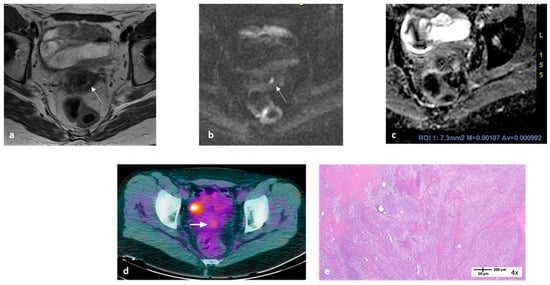

- Valentini, A.L.; Miccò, M.; Gui, B.; Giuliani, M.; Rodolfino, E.; Telesca, A.M.; Pasciuto, T.; Testa, A.; Gambacorta, M.A.; Zannoni, G.; et al. The PRICE study: The role of conventional and diffusion-weighted magnetic resonance imaging in assessment of locally advanced cervical cancer patients administered by chemoradiation followed by radical surgery. Eur. Radiol. 2018, 28, 2425–2435. [Google Scholar] [CrossRef] [PubMed]

- Gui, B.; Miccò, M.; Valentini, A.L.; Cambi, F.; Pasciuto, T.; Testa, A.; Autorino, R.; Zannoni, G.F.; Rufini, V.; Gambacorta, M.A.; et al. Prospective multimodal imaging assessment of locally advanced cervical cancer patients administered by chemoradiation followed by radical surgery-the “PRICE” study 2: Role of conventional and DW-MRI. Eur. Radiol. 2019, 29, 2045–2057. [Google Scholar] [CrossRef] [PubMed]

- Rufini, V.; Collarino, A.; Calcagni, M.L.; Meduri, G.M.; Fuoco, V.; Pasciuto, T.; Testa, A.C.; Ferrandina, G.; Gambacorta, M.A.; Campitelli, M.; et al. The role of (18)F-FDG-PET/CT in predicting the histopathological response in locally advanced cervical carcinoma treated by chemo-radiotherapy followed by radical surgery: A prospective study. Eur. J. Nucl. Med. Mol. Imaging 2020, 47, 1228–1238. [Google Scholar] [CrossRef] [PubMed]